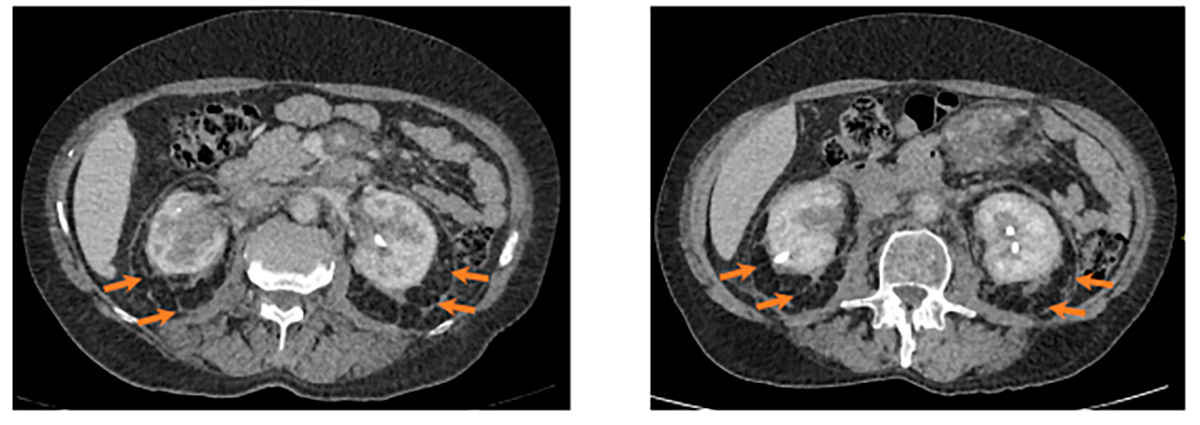

Рис. 5. Утолщение паранефральных перегородок с обеих сторон по типу «волосатых» почек (“hairy” kidney). Слева 2025 год, справа 2023 год. Аксиальная проекция.